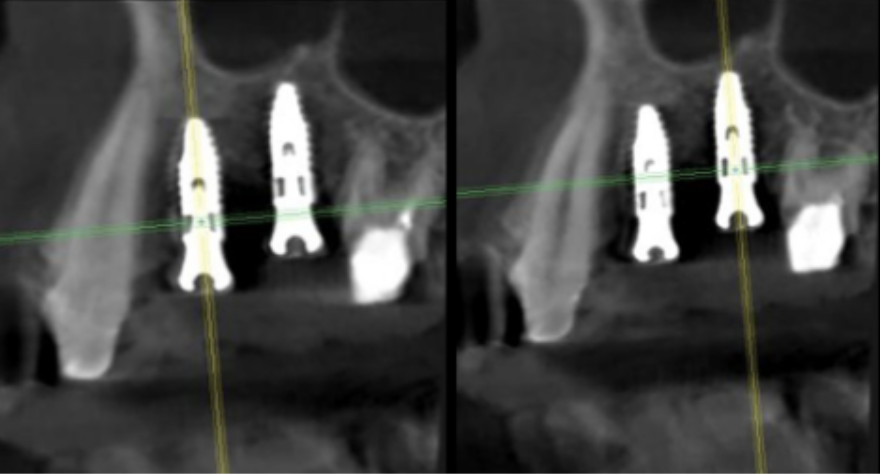

インプラント

サージカルガイドの作成

インプラント埋入前のCTによる確認